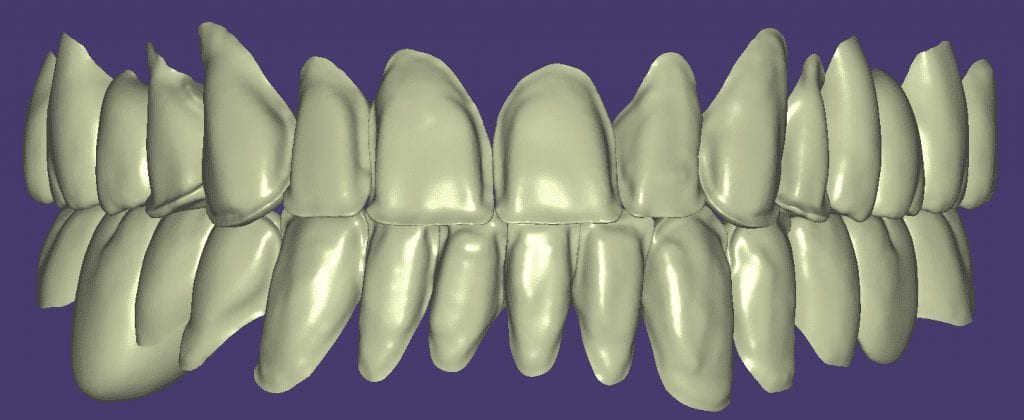

Once the appropriate library is chosen, the digital wax ups are performed. In the subsequent photos you can see the transparent overlay of the wax-ups to the original position of the existing dentition

Over the course of a few appointments, the vertical dimension was reduced and the temporaries were adjusted to the patient’s desires. The new upper and lower arch were captured with the Medit i500 and the jaws were related to each other.

This was then imported into exocad where the prepped arches from a few weeks prior were force matched to the new bite

After the upper jaw was related to the temps, the same was done with the lower arch. Great care was taken to make sure the arches were properly related to each other throughout the process